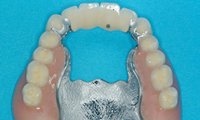

몇 개의 임플란트를 심은 뒤, 완성된 임플란트에 부분 틀니를 연결해

흔들림 없이 안정감 있게 사용할 수 있으며 스스로 탈착은 불가능합니다.